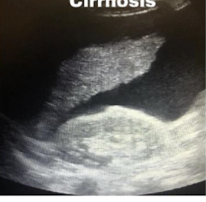

What is this and what type of scan

colon polyp, barium enema

Colon polyp, CT